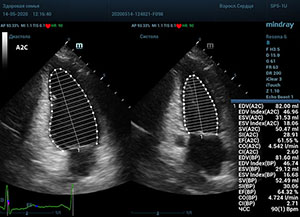

С появлением В режима реализовалась возможность визуализации всех сегментов миокарда из парастернальных и апикальных сечений. Метод Teicholtz в широкой практике сменился методом дисков. Метод дисков, или метод Simpson, позволяет разбить левый желудочек на 20 дисков, с расчетом объема каждого из них. Используя 2 перпендикулярных сечения, апикальные двух и четырех камерное, мы приближаемся к значению реального объема левого желудочка. Исследователь обводит интерфейс эндокард – кровь в фазу диастолы и фазу систолы. Линия простирается от кольца митрального клапана и до кольца митрального клапана, четко разграничивая объем желудочка от предсердия. Для достоверного изменения необходимо использовать ЭКГ канал.

Обводить вручную эти линии занимало много времени, однако результат того стоил. Следующим шагом стало появление Spline технологии, позволяющее расставлять точки и автоматически их соединять. Такой способ планиметрии контура эндокарда значительно сократил время измерения.

Что могут предложить современные приборы? Приборы нашего времени являются мощными вычислительными машинами, способными обрабатывать полученную информацию даже без помощи человека. Система автоматического вычисления фракции выброса – AUTO EF на

приборах серии Resona компании Mindray сделает все за вас. За пару секунд прибор сам отыщет нужную фазу сердечного цикла и произведёт измерение и расчеты, а также покажет график изменения объема в сердечном цикле. От Вас требуется только получить качественное 4С и 2С сечение. Впрочем, прибор всегда оставляет возможность коррекции, если доктор имеет свое мнение на расположение точек планиметрии или момента измерения по ЭКГ каналу.